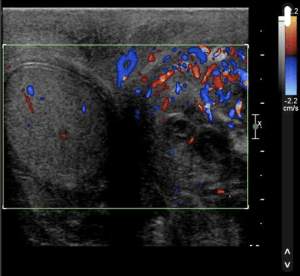

USS is especially useful in patients with sudden onset pain to assess for Testicular Torsion (no flow on colour doppler in many cases) and to assess for Epididymo-orchitis (increased flow in many cases)

Ultrasound 1 Epididymo-orchitis – “Testicular US demonstrates increased vascularity in the left testis and epididymis in keeping with epididymoorchitis. There is also a left sided hydrocele.